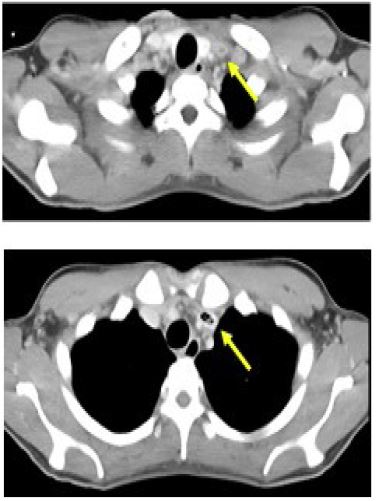

The results of the blood tests and Computed Tomography (CT) scans are displayed in Table 3. The levels of inflammatory markers displayed a significant increase, whereas the markers of renal function and coagulation were also severely impaired. Plain CT scan revealed multiple bilateral shadows in the lungs (Figure 1). We assessed multiple organ failure as a result of sepsis caused by soft tissue infection or pneumonia of the COVID-19. However, contrast-enhanced CT revealed a low-density intraluminal thrombus in the left jugular vein (Figure 2). We diagnosed LS and assessed lung shadows and soft tissue swelling as secondary findings.

Figure 1: The plain CT scan revealed multiple shadows in the bilateral lung.